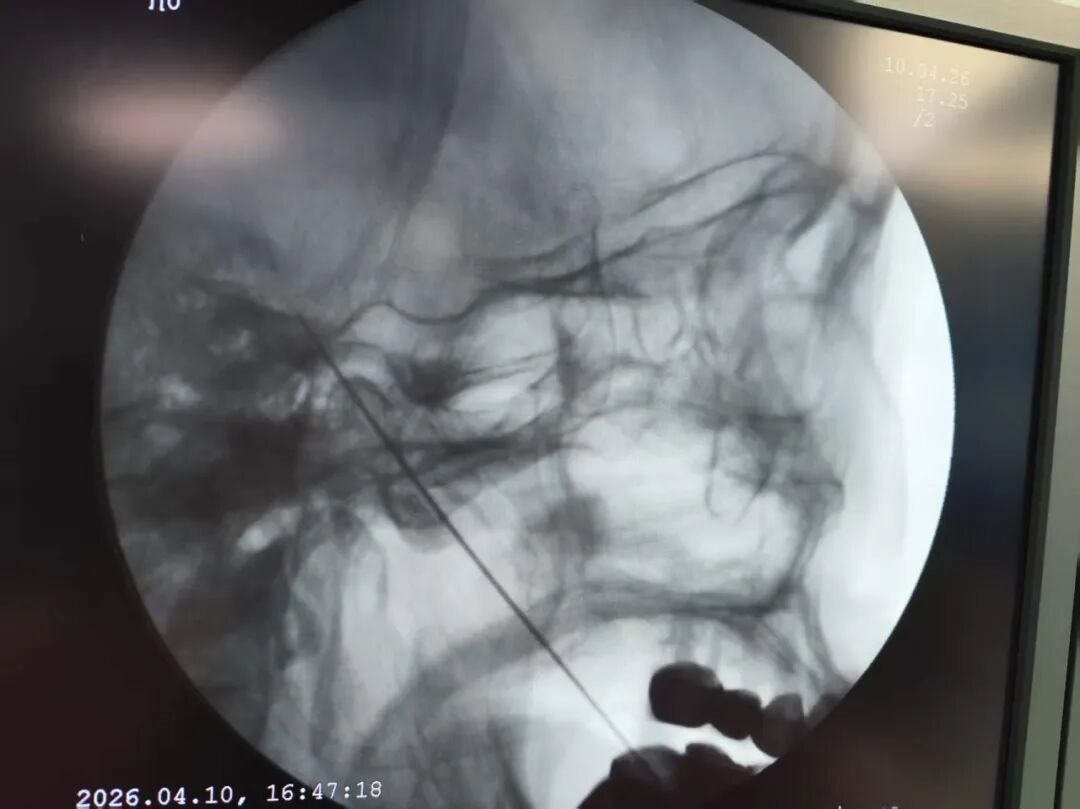

▲ C臂X线引导下三叉神经穿刺定位

借助高清CT或X线引导,像装了GPS,射频针精准直达疼痛根源,避开周围重要组织,哪疼治哪。